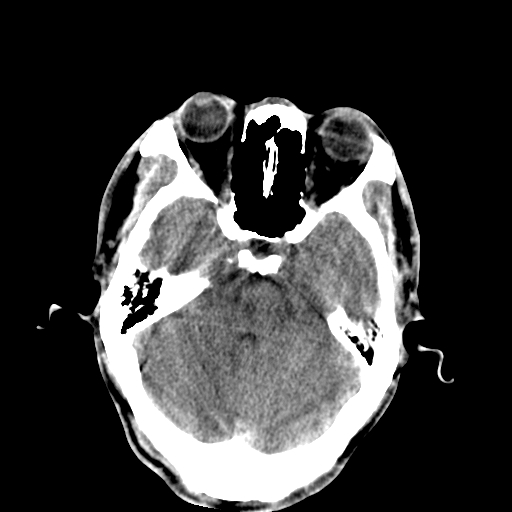

以下是引用李衡钧在2008-9-18 17:37:00的发言:[br]脑质内见两个低密度灶,其内见点状高密度。[br]考虑脑囊虫。建议增强或进一步检查确诊。

以下是引用chmh在2008-9-18 18:45:00的发言:[br]考虑脑囊虫病可能性大,建议行ct增强检查及血清和脑脊液囊虫补体结合试验.